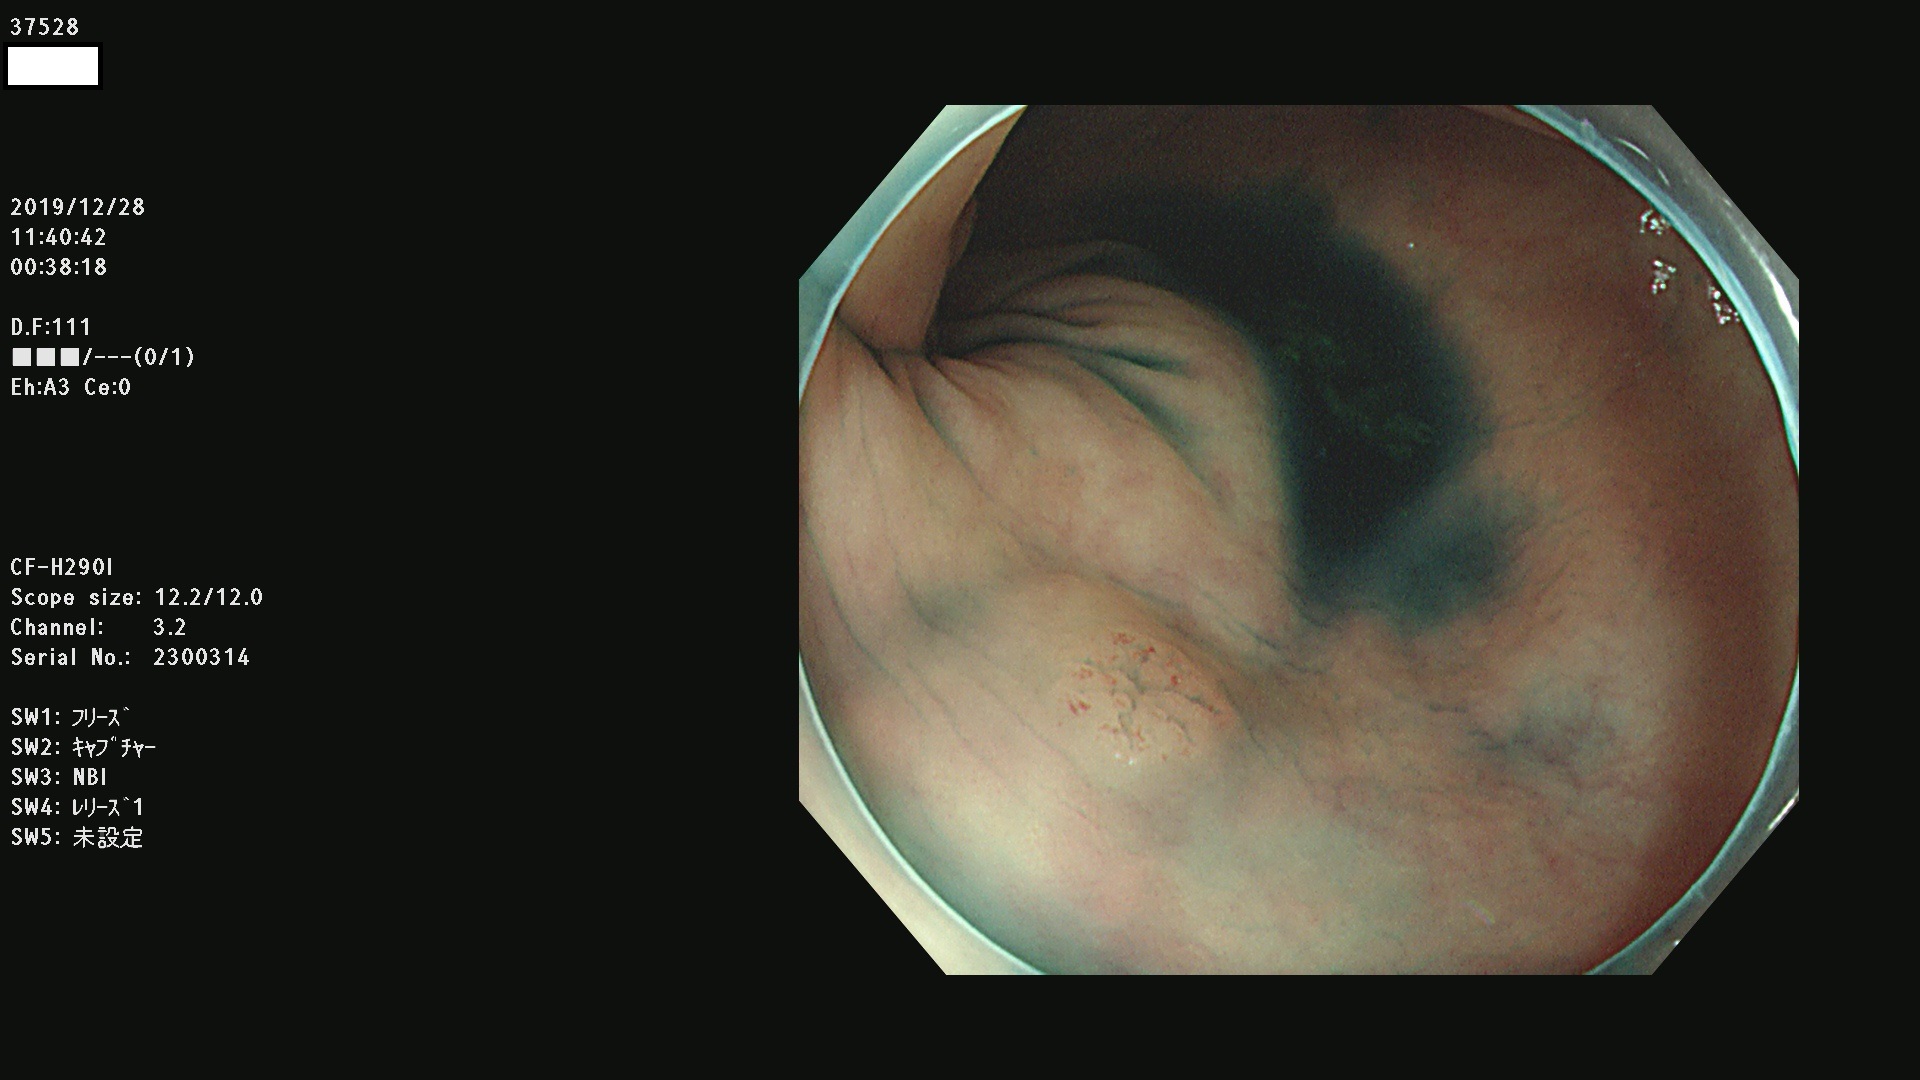

発見困難で危険性の高い平坦型病変(上記100名より抽出) ![]()